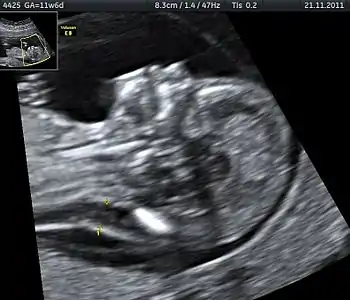

Ultrasound is often used to diagnose stillbirth and medical conditions that raise the risk.

Diagnostic methodNo fetal movement felt, ultrasound[5]

Often the cause is unknown.[1][12] Causes may include pregnancy complications such as pre-eclampsia and birth complications, problems with the placenta or umbilical cord, birth defects, infections such as malaria and syphilis, and poor health in the mother.[2]:Causes tab,[3][13] Risk factors include a mother's age over 35, smoking, drug use, use of assisted reproductive technology, and first pregnancy.[4] Stillbirth may be suspected when no fetal movement is felt.[5] Confirmation is by ultrasound.[5]

It is unknown how much time is needed for a fetus to die. Fetal behavior is consistent and a change in the fetus' movements or sleep-wake cycles can indicate fetal distress.[30] A decrease or cessation in sensations of fetal activity may be an indication of fetal distress or death,[31] though it is not entirely uncommon for a healthy fetus to exhibit such changes, particularly near the end of a pregnancy when there is considerably less space in the uterus than earlier in pregnancy for the fetus to move about.[32] Still, medical examination, including a nonstress test, is recommended in the event of any type of any change in the strength or frequency of fetal movement, especially a complete cease; most midwives and obstetricians recommend the use of a kick chart to assist in detecting any changes.[33] Fetal distress or death can be confirmed or ruled out via fetoscopy/doptone, ultrasound, and/or electronic fetal monitoring.[34] If the fetus is alive but inactive, extra attention will be given to the placenta and umbilical cord during ultrasound examination to ensure that there is no compromise of oxygen and nutrient delivery.[35]